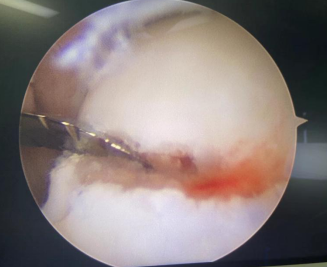

关节镜下左踝关节清理

术中前踝所见(游离骨折块)

4月12日一早,患者被推进了手术室。石荣剑副院长、曹广超主任、胡帆医生手术团队为患者进行了“关节镜下左踝关节清理+机器人辅助左距骨、右跟骨骨折复位内固定术”。手术两小时顺利完成。